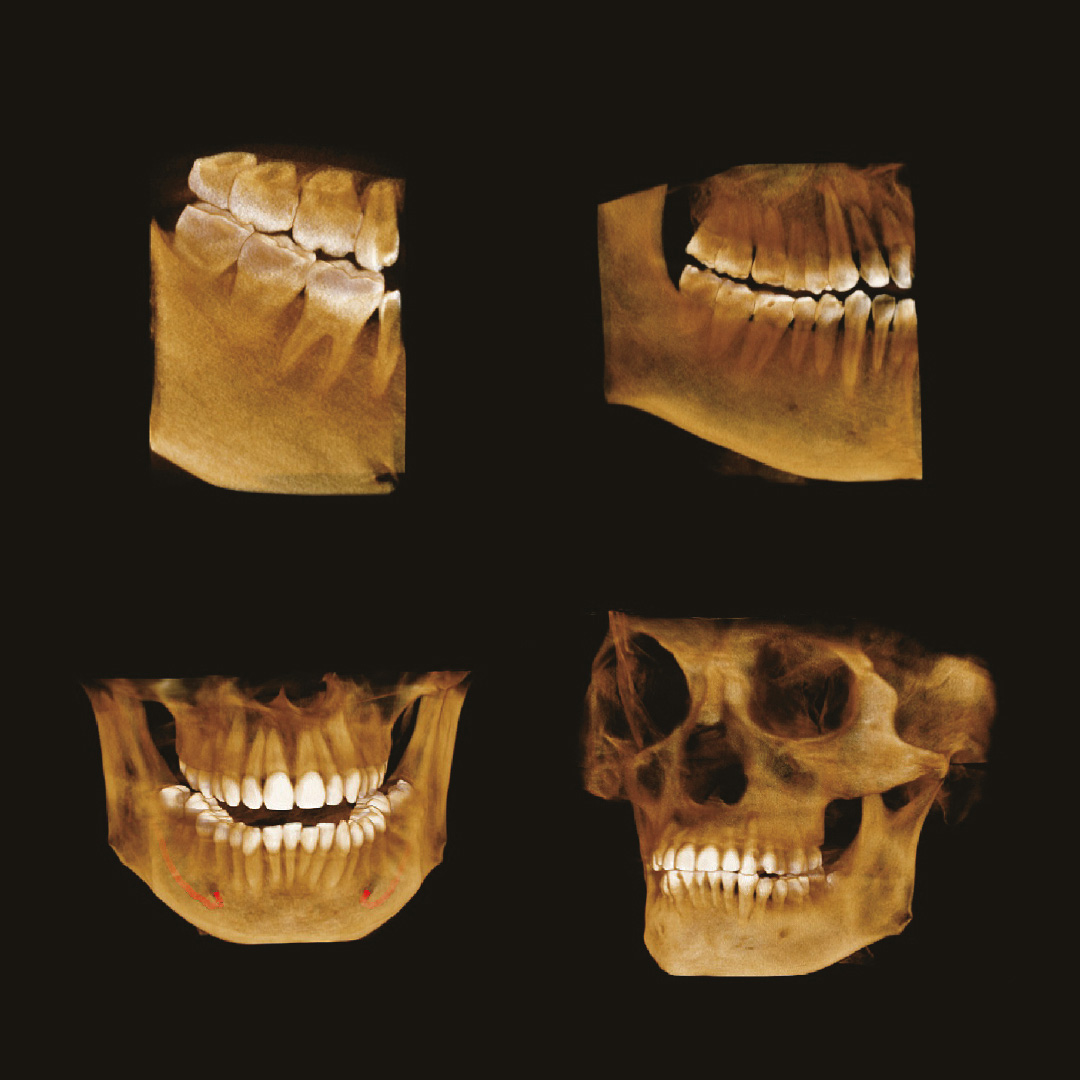

Современная стоматология уже давно не работает вслепую, и каждому из направлений стоматологии необходимо проводить рентгеновские исследования:

Стоматолог-терапевт по снимку видит не только кариес, а также способен оценить, как периодонтальные ткани, так и различные воспалительные процессы затрагивающие пульпарную камеру.

Стоматолог-хирург не способен производить свои манипуляции без снимка КТ, иначе он будет вынужден действовать вслепую, не сумев оценить анатомию области вмешательства.

Стоматолог-ортопед не сможет гарантировать надежность конструкции без правильной оценки стабильности опорных зубов при помощи снимка КТ.

Стоматологу-ортодонту, чтобы правильно простроить план лечения, помимо слепков, так же нужен снимок КТ.